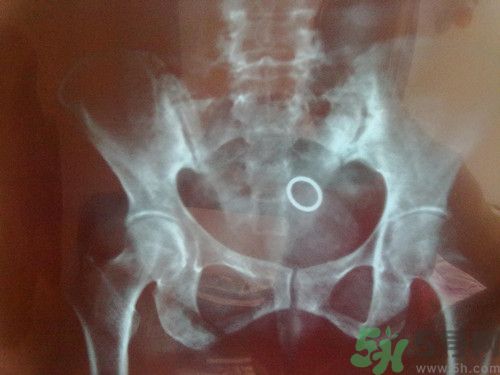

今天微博都被周杰倫患脊柱炎的消息刷爆了,脊柱炎到底是什么病呢?聽著好嚴重的樣子?能不能治好呢?下面我們來一起看看具體內(nèi)容!

1.強直性脊柱炎。年輕人發(fā)病多,一般不超過三十歲,男性多于女性。